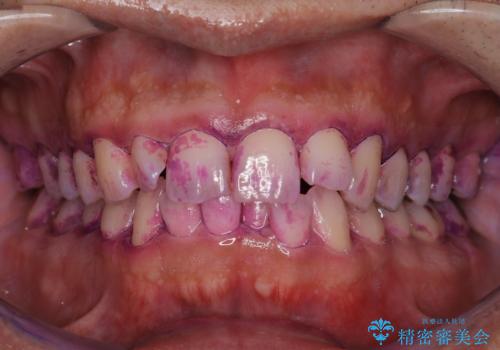

染め出しとは

染め出しとは、専用の薬剤を使ってプラーク(歯垢)を赤く染め出すものです。

プラーク(歯垢)は歯と同じような色をしているので、見ただけではどれくらい付いているのかとてもわかりにくいです。

染めだしをすることにより、歯磨きの仕方のくせや、磨き残しを一目で把握でき、改善していくことが可能です。